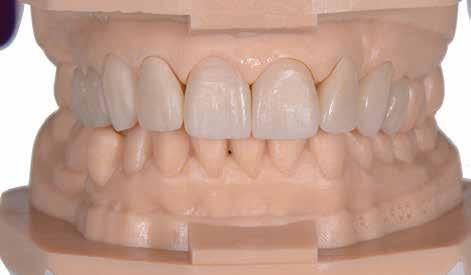

A szájüregi vizsgálat során nem találtunk szuvas léziók jelenlétére utaló eltéréseket. A nagymetszőfogakon megfigyelhető jelentős mértékű kopás ellenére nem észleltünk craniomandibuláris diszfunkció jelenlétére utaló jeleket. A vizsgálat befejezését követően a pácienst tájékoztattuk a különböző kezelési lehetőségekről. Az esztétikai megjelenés javítása érdekében először egy alignerekkel végzett fogszabályzó kezelés elvégzését, majd a harapási helyzet optimalizálását követően a felső frontfogai kompozittal történő direkt felépítését vagy héjakkal történő ellátását (pl.: non-prep héjak) javasoltuk (3. és 4. ábra).

A fogazat minimálinvazív módon készített héjakkal történő ellátásához a fogaknak olyan pozícióban kell lenniük, amely lehetővé teszi az esztétikai megjelenés additív eljárások alkalmazása mellett történő optimalizálását.1. ábra: Kiindulási állapot. A felső nagymetszőfogak élharapásban vannak. 2. ábra: Az orthodonciai kezelés megkezdése előtt készített intraorális felvétel. A páciens csak óvatosan mer mosolyogni. 3. és 4. ábra: Digitálisan megtervezett kezelés.

A kezelések második fázisában a pácienssel közösen non-prep/ minimálinvazív héjak készítése mellett döntöttünk (6. és 7. ábra).